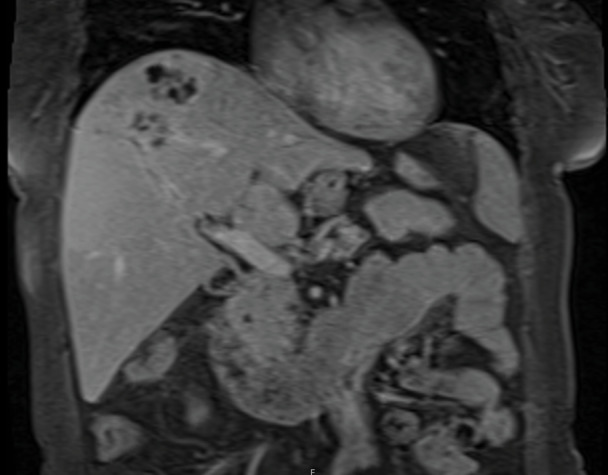

A 57-year-old female patient presented with fever, nausea, vomiting, loss of appetite, and weight loss within the last two months. Ceftriaxone and metronidazole therapy was started upon discovery of a liver abscess but provided no benefit. Following the of abscess biopsy, the patient developed fever, itching, anemia, acute renal failure, hyperbilirubinemia, and eosinophilia that required intensive care unit (ICU) admission. The Fasciola hepatica antibodies were detected by enzyme-linked immunosorbent assay (ELISA). Triclabendazole was started, after which the symptoms and magnetic resonance imaging (MRI) findings regressed. Even without eosinophilia, F. hepatica should be considered in cases with a liver abscess that does not respond to antibiotics.

Abstract Image